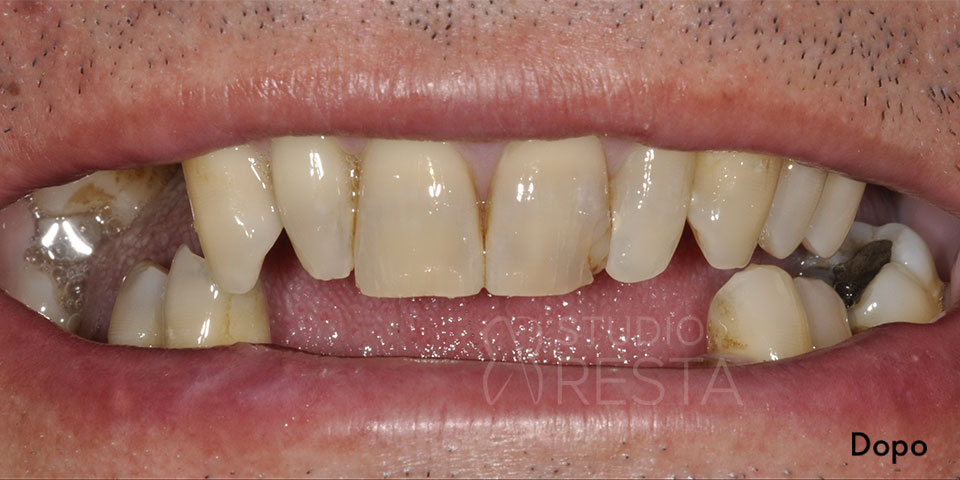

All on Four Senza Gengiva Finta

L’implantologia All on Four senza gengiva finta è un’opzione protesica che non prevede l’utilizzo sulle protesi dentali di gengiva artificiale. Questo approccio consente un’estetica migliore e soprattutto un aspetto più naturale delle protesi in modo da renderle perfettamente mimetizzabili.